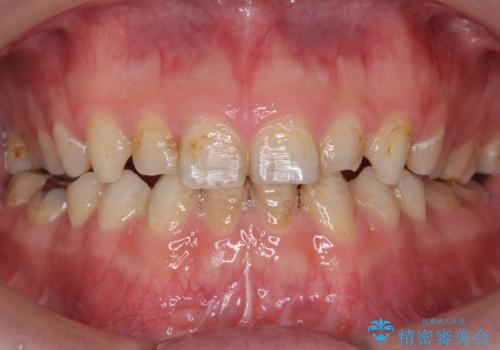

30代女性 ミゼラブルな前歯の陥没を再生する③完成へ

- 他院にて前歯を抜歯され、その後の組織の吸収によりシビアな欠損を伴う状態であった

→2度の手術により失われた骨・および軟組織の再生を図り、最終的にセラミックにて修復を終えた

完成

骨造成と2次的な結合組織の付着により

・歯牙を支持する歯槽骨の回復

・浅いポケットの獲得

・最低限の審美性の回復

が達成された。

長期的な経過は予測できないため、定期的なチェックに来ていただき、レントゲンなどによる継続的な評価をしていきたい。

被せものの種類:ジルコニアオールセラミック スタンダード